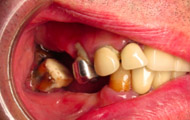

Situation clinique initiale

Situation clinique terminée